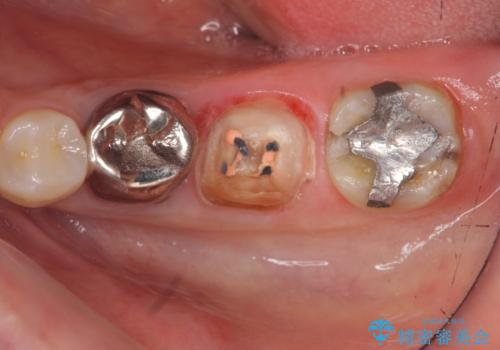

- 大人になってからも残っていた乳歯が揺れ始め、抜歯を覚悟しインプラント治療を希望して来院されました。

X線写真より、乳歯は抜歯が必要な状態でインプラントは小臼歯の埋伏により難しい状況であったのでブリッジによる補綴を選択しました。

ブリッジ治療の予知性を高めるために、虫歯の徹底的な除去に加え縁上歯質を確保するための歯周外科手術、マイクロスコープを用いた精密根管治療を行う治療計画としました。